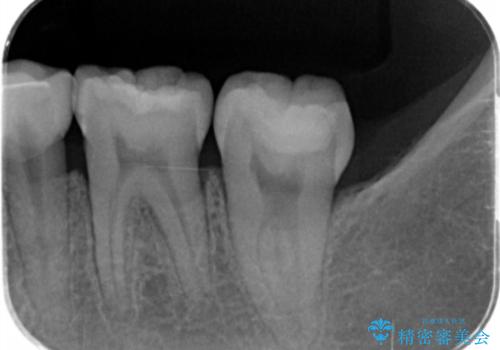

- 出産して落ち着いたから虫歯のチェックをしてほしいとのことで来院されました。

左下の奥歯に詰まっている樹脂の周辺が虫歯になっていたため、治療を進めていくこととなしました。

- 左下7 仮歯+e-maxクラウン:11,000円+77,000円費用は治療当時の料金となります

今回の場合、虫歯の大きさが大きく本来であれば歯茎に対しても治療をすることが検討されケースですが、ご希望されなかったため被せ物のみでの治療となりました。